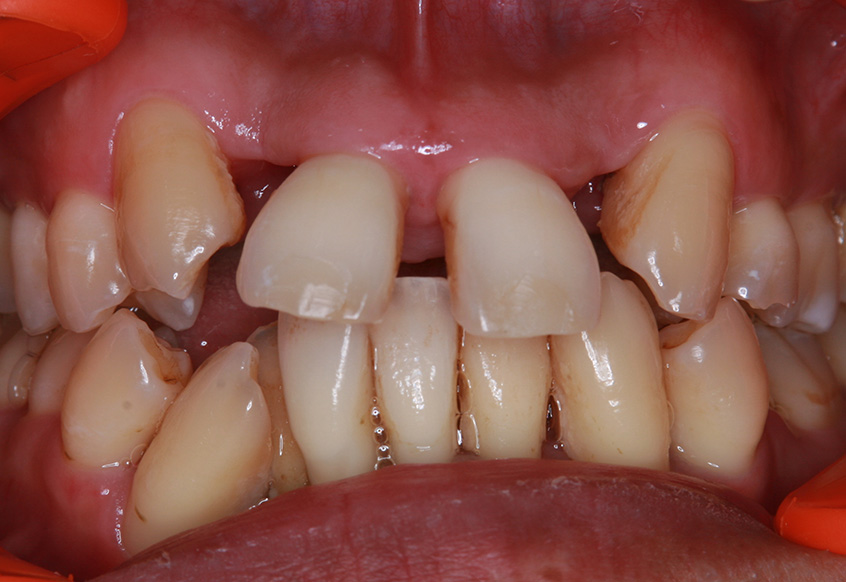

親知らずの痛みがなくなった患者さんは、昔から歯並びが気になっていることを打ち明けてくれました。特に上の歯が少し前に出ていたり、隙間があったりしている点を治したいそうです。そこで、まず上の歯並びの矯正治療を開始しました。

最初のお口の中 ワイヤー装着して治療を開始

-

| 主訴 | 上の前歯の歯並びを整えたい |

| 診断 | 歯列不正、う蝕歯 |

| 治療内容 | 上顎側切歯を2本抜歯した後、上顎の歯にブラケットを装着し、ワイヤー、矯正用ゴムで歯の移動を行いました。その後、被せ物の治療を行って治療を終了しています。 |